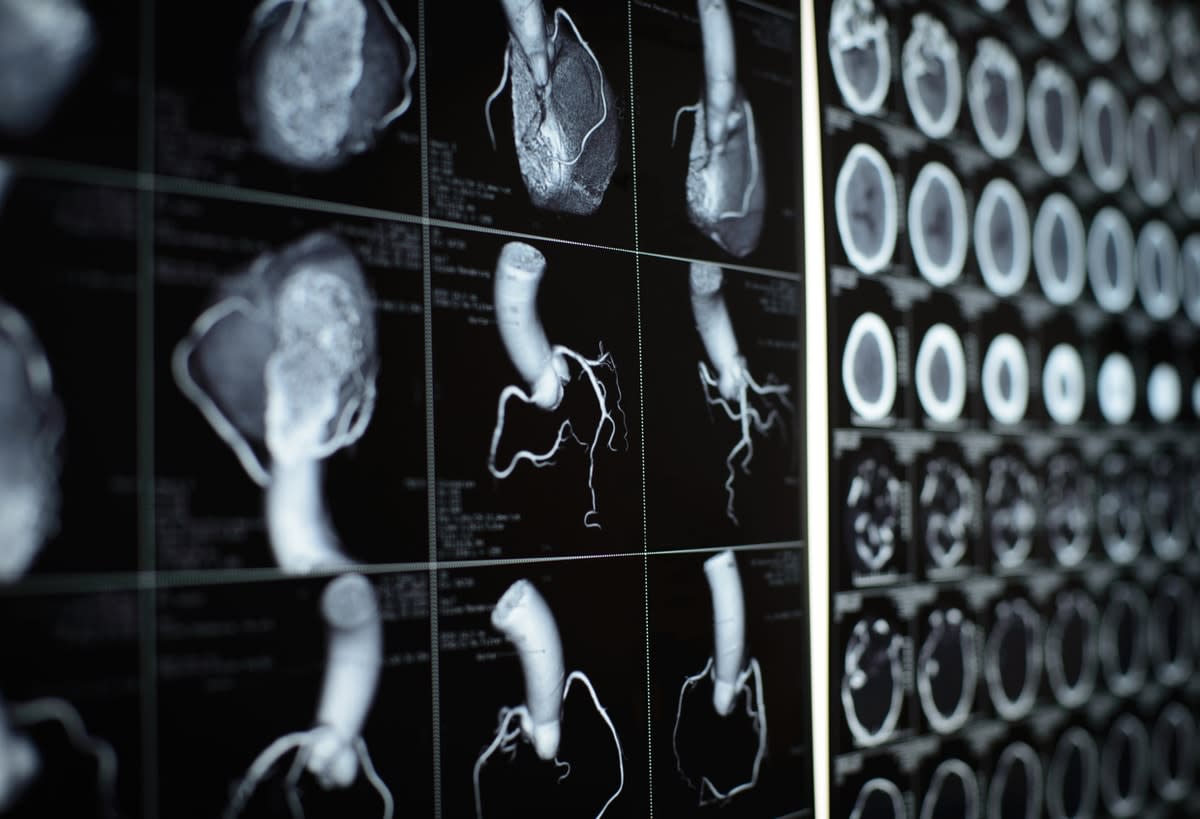

x-rays